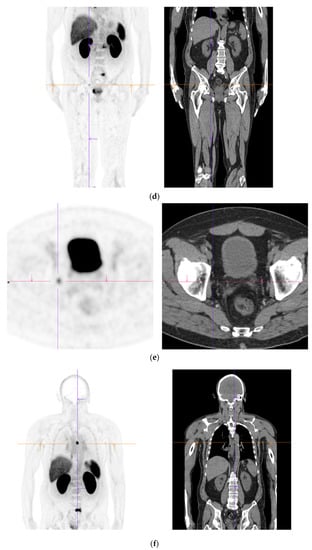

Figure 1.

PSMA PET-CT scan showing normal distribution of PSMA-11. 60 yr old M—Gleason 6 prostate cancer on active surveillance for past 2 years; PSA 7.2; MR imaging—low grade changes PIRADS 2. PSMA PET-CT: 68Ga-PSMA - 204 MBq; uptake 52 min; BMI = 29.7; Wt 90 Kg; coronal PET and corresponding CT slices (soft tissue windows) from left to right. (a)—physiological uptake in lacrimal, submandibular salivary glands, parotid glands, retropharyngeal soft tissue, liver, bowel, part of spleen and pooling of tracer in bladder; mild reactive tracer uptake in groin and axillary nodes. (b)—physiological uptake in head and neck; reactive uptake axillary nodes; focal uptake in apex of prostate gland anterior below the bladder SUV = 9.1; marked uptake/excretion of tracer in both kidneys.